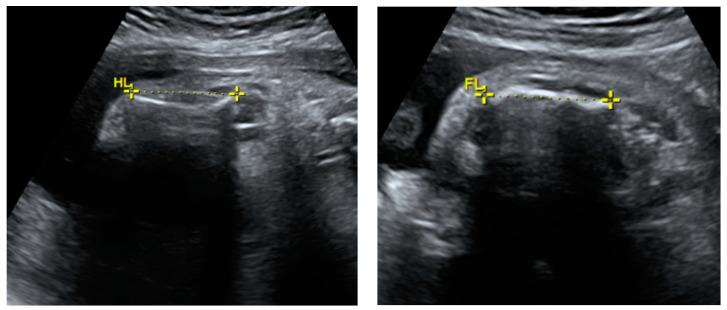

Osteogenesis imperfecta (OI), also known as brittle bone disease, belongs to a rare heterogeneous group of inherited connective tissue disorders. In experienced prenatal centers, severe cases of OI can be suspected before birth from the first trimester prenatal ultrasound screening. In this article, we describe a case report of OI suspected at the 26th week of gestation and the patient's outcomes in infancy one year after birth, as well as compare our case to other prenatally or soon-after-birth suspected and/or diagnosed OI clinical case reports in the literature. This case was managed by a multidisciplinary team. In this clinical case, OI was first suspected when prenatal ultrasound revealed asymmetric intrauterine growth restriction and skeletal dysplasia features. The diagnosis was confirmed after birth using gene variant detection via exome sequencing; the gene variant causes OI types I-IV. The familial history was negative for both pregnancy-related risk factors and genetic diseases. At one year old, the patient's condition remains severe with bisphosphonate therapy.